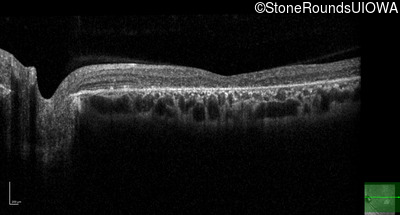

All three of the cardinal ophthalmic features of Mendelian macular dystrophies are present in this patient. The most striking features of the fundus exam are the numerous yellow flecks at the level of the RPE. Flecks are most commonly seen in AR Stargardt disease and pattern dystrophy although they may be seen in some of the rarer Mendelian maculopathies as well. The visual acuity in patients with AR Stargardt disease is often "worse than the fundus looks" while the acuity in pattern dystrophy is often quite good despite extensive flecks. The pedigree of this patient is compatible with ABCA4-associated Stargardt disease and the better than expected acuity is attributable to foveal sparing (see below). The onset of reduced acuity at age 10 is much more characteristic of ABCA4 disease than pattern dystrophy. Another feature present in this patient that is very frequently seen in Stargardt disease is peripapillary sparing. However, this sign can be seen in pattern dystrophy as well. When central atrophy is present in ABCA4-associated Stargardt disease it often somewhat shiny (which is uncommon with the geographic atrophy of pattern dystrophy or age-related macular degeneration). Some patients with ABCA4-associated Stargardt disease can have some preservation of the fovea giving a zonal "bullseye" appearance to the center of the macula. Sometimes this preservation is associated with preserved acuity as in this case. The outer nuclear layer (ONL) is much thinner than normal on OCT, indicative of photoreceptor loss. This is associated with a thinning of the ellipsoid zone which is usually many times brighter and thicker than the external limiting membrane (ELM). These two lines are essentially equal in intensity in this patient. The foveal sparing is seen on OCT only as a small bit of retinal convexity in the center of the atrophy coupled with a small bit of residual RPE flanked by bare Bruch's membrane. The presence of a robust I2e isopter on Goldmann perimetry places this patient in the least severe half of all Stargardt patients (see Schindler, et al., 2010). Most patients with ABCA4-associated disease are somewhat myopic as is this patient. Stargardt patients also tend to perform very poorly on pseudoisochromatic plates, even when their acuity is still fairly good as it is here.